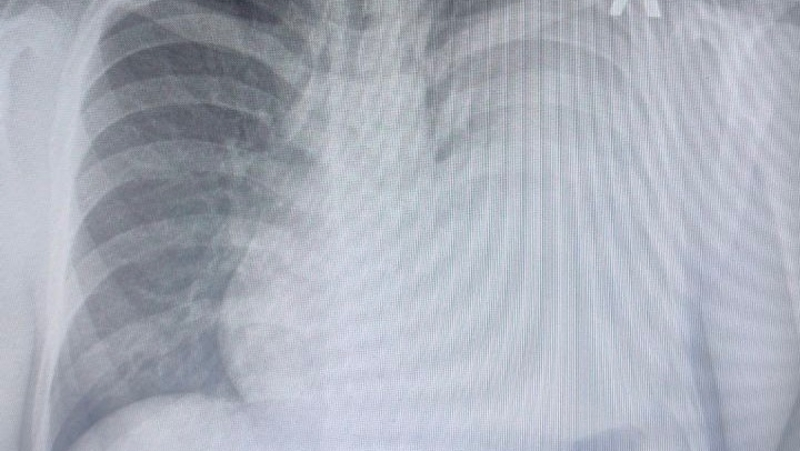

По её рекомендации родители обратились в краевую детскую клиническую больницу. Врачи быстро установили, что это энцефалопатия. В итоге удалось добиться выдачи противоэпилептического препарата через поликлинику по месту жительства и минздрав Ставропольского края. Илона Марьясова уточнила, что сейчас ребёнок получает повышенную дозу и чувствует себя нормально.